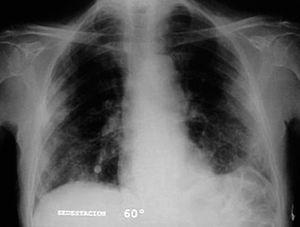

Varón de 74 años, ex fumador de 37 paquetes-año, sin alergias conocidas, diagnosticado de ELA hacía 10 meses y en tratamiento con Rilutek® (riluzol), a dosis de 50 mg/12 h, desde hacía 5 meses, que 45 días antes del ingreso en nuestro centro había iniciado un cuadro clínico consistente en tos no productiva. Inicialmente había recibido tratamiento con amoxicilina-ácido clavulánico a dosis de 875 mg-125 mg/8 h durante 18 días, hasta 5 días antes de su ingreso, con progresivo deterioro clínico consistente en incremento de la tos no productiva, disnea de reposo, astenia, sudación profusa, taquipnea, sin objetivar fiebre durante todo el período de evolución del proceso. En la exploración efectuada en el momento del ingreso hospitalario estaba afebril, con una presión arterial de 110/60 mmHg, frecuencia cardíaca de 94 lat/min y frecuencia respiratoria de 24 respiraciones/min. Se apreció una disminución de la amplitud de los movimientos respiratorios sin otros hallazgos de interés. La gasometría arterial con oxígeno en gafas a 2 l/min mostró los siguientes valores: pH de 7,46, presión arterial de oxígeno de 67 mmHg, presión arterial de anhídrido carbónico de 44 mmHg y HCO3 de 31 mEq/l. En la analítica, el hemograma presentó 6.200 leucocitos (un 68% neutrófilos y un 1% eosinófilos) y una velocidad de sedimentación globular de 74 mm en la primera hora. Existía elevación de las cifras de fibrinógeno (715 mg/dl), inmunoglobulina (Ig) G (1.960 mg/dl; IgG1: 1.310 mg/dl; IgG4: 280 mg/dl), IgA (498 mg/dl), IgE (299 KU/l) y proteína C reactiva (20 mg/l). El resto de las determinaciones analíticas, incluidos los parámetros hematológicos, glucemia, iones, parámetros de función renal, hepáticos, lactatodeshidrogenasa y sus isoenzimas, enzima de conversión de la angiotensina, IgM, anticuerpos antinucleares, anti-ADN, anticuerpos anticitoplasma de neutrófilo y marcadores tumorales séricos, estaban dentro de los valores considerados normales. La prueba de Mantoux, las serologías frente a gérmenes atípicos y virus respiratorios, así como las determinaciones en orina para Legionella pneumophila serotipo 1 y Streptococcus pneumoniae, fueron negativas. A pesar de estar afebril, durante su ingreso se extrajeron hemocultivos, sin que se aislara ningún germen. El paciente no expectoraba, por lo que no se pudieron obtener muestras para procesamiento bacteriológico. El electrocardiograma y un ecocardiograma no objetivaron anomalías. Las pruebas cutáneas a una batería de neumoalergenos habituales, entre ellos ácaros, pólenes de malezas, árboles, gramíneas, hongos y epitelios, fueran negativos. La radiografía y la tomografía computarizada de tórax mostraron infiltrados alveolointersticiales bilaterales (figs. 1 y 2).

Fig. 1. Infiltrados pulmonares bilaterales de predominio periférico.

Dada la ausencia de fiebre, leucocitosis y semiología de infección respiratoria, se sospechó que la afectación pulmonar podía ser secundaria al riluzol, único fármaco que recibía el paciente. Se retiró el medicamento y se inició tratamiento con 40 mg diarios de metilprednisolona durante 6 días, al cabo de los cuales se interrumpió. A las 72 h ya era manifiesta la disminución del grado de disnea, de la astenia y de los infiltrados, así como el incremento de la saturación de oxígeno. Al cabo de una semana los infiltrados habían desaparecido y la espirometría mostraba los siguientes valores: capacidad vital forzada (FVC) de 1,34 l (33%), volumen espiratorio forzado en el primer segundo (FEV1) de 1,32 l (47%) y FEV1/FVC del 99%. La saturación de oxígeno basal era del 95% y no había desaturación en el test de la marcha de los 6 min. Posteriormente, en el seguimiento realizado no reaparecieron los infiltrados y el paciente falleció al cabo de 8 meses debido a la ELA.